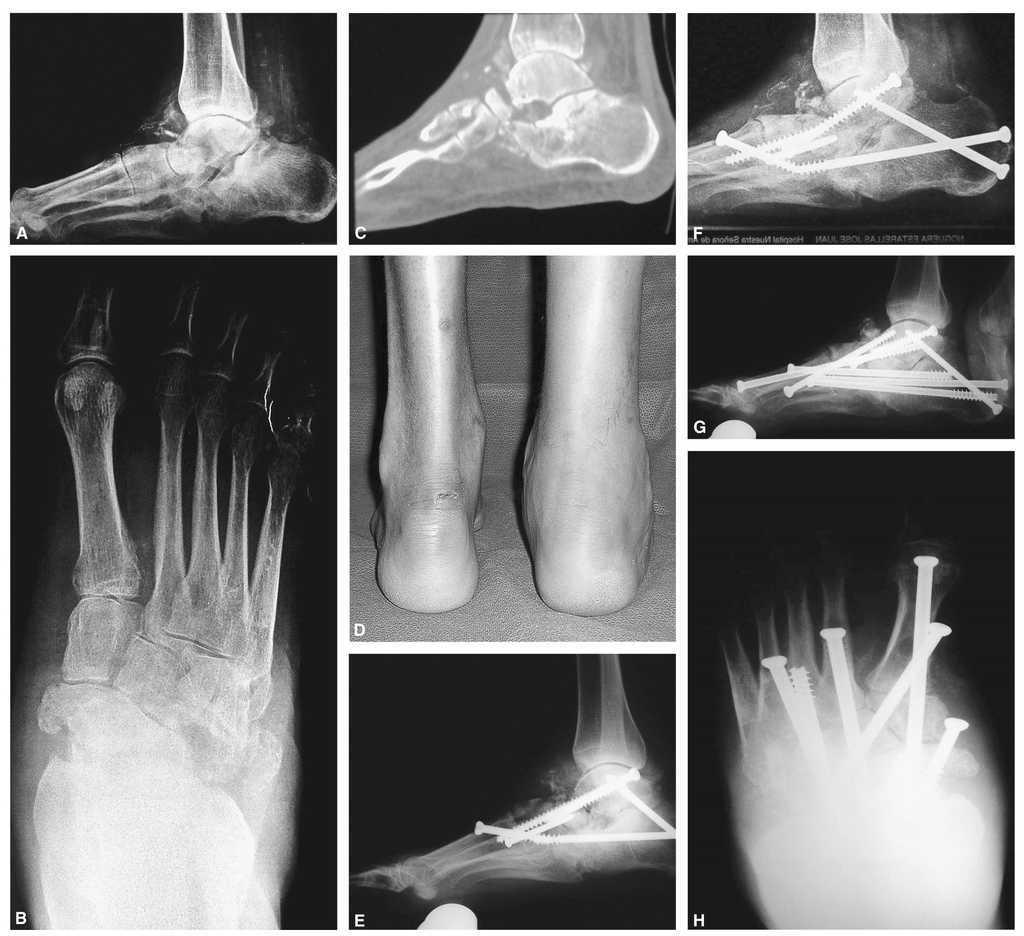

La pseudoartrosis es una complicación que puede ocurrir, especialmente en los primeros estadios del pie de Charcot, cuando el hueso es blando. Incluso con las mejores técnicas de fijación, el 15% de los pacientes desarrollarán una pseudoartrosis en una o más articulaciones, algunas de las cuales serán asintomáticas. El porcentaje es mayor en fumadores y en pacientes con hueso avascular. Si se rompen los tornillos se tiene que proceder a la revisión de la artrodesis y del alineamiento, empleando tornillos percutáneos adicionales y, posiblemente, injerto (fig. 3). Si los tornillos se rompen y no causan prominencias óseas, no hace falta una nueva cirugía. Se puede tolerar un grado moderado de consolidación en mala posición, y si no causa lesiones por presión con el calzado, no es necesaria la revisión. En caso contrario se debe reintervenir al paciente. A veces se puede realizar una manipulación para mejorar la posición del pie, retirar uno o más tornillos colocados anteriormente e introducir otros más largos y resistentes. Así no se vuelven a disecar las partes blandas y, si la revascularización ha ocurrido en esa área, la curación tendrá lugar en un tiempo razonablemente rápido.

Figura 3. A: pie derecho de un varón de 35 años de edad con diabetes mellitus tipo 1, visto en una proyección lateral en carga, en la que se aprecia colapso a nivel de la articulación astragaloescafoidea con desintegración del cuello y cabeza del astrágalo. La articulación calcaneocuboidea y subastragalina también están destruidas. El ángulo del calcáneo es inferior a 30° y existen numerosos fragmentos óseos en torno al astrágalo y articulación del tobillo. B: proyección anteroposterior que muestra la desintegración de la articulación de Chopart con acortamiento del pie. C: un corte sagital del escáner muestra la fragmentación de la tuberosidad anterior del calcáneo, con desaparición de la cabeza y cuello del astrágalo. D: visión posterior el paciente, que presenta tumefacción y deformidad del retropié. E: proyección lateral intraoperatoria simulando carga en la que se observa una triple fusión posterior que se extiende a la columna medial. El tornillo entre el primer metatarsiano y el astrágalo se ha introducido de manera retrógrada, primero perforando desde el primer metatarsiano al astrágalo y después un tornillo completamente roscado se coloca desde el astrágalo al primer metatarsiano. Se ha mejorado el alineamiento. F: seis meses después se ha producido un fallo con rotura de un tornillo y colapso a nivel de la articulación de Chopart. G: el paciente fue intervenido de nuevo, retirando el tornillo roto parcialmente e introduciendo tornillos largos a través de todos los metatarsianos excepto del quinto. Se colocó un tornillo canulado largo de 7,3 mm intramedular desde la cabeza del primer metatarsiano en la columna medial hasta el cuerpo del astrágalo. Se añadió aloinjerto y autoinjerto. H: una radiografía dorsoplantar muestra el buen alineamiento y cada metatarsiano, excepto el quinto, se estabilizó con tornillos largos. Se produjo la consolidación y el paciente volvió a su vida normal como actor.